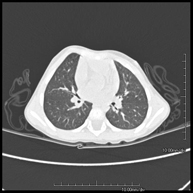

Prueba diagnóstica que consiste en el estudio de las arterias pulmonares mediante el empleo de un equipo de TC (Tomografía Computarizada) obteniendo imágenes bi y tridimensionales. En este estudio es imprescindible el uso de contraste yodado, el cual permitirá una mejor definición anatómica. Esta prueba está principalmente indicada en los casos de sospecha de tromboembolismo pulmonar (TEP) para descartar o confirmar la presencia de coágulos sanguíneos en el interior de las arterias. - TC Tórax alta resolución

Prueba diagnóstica que consiste en el estudio del pulmón mediante el empleo de un equipo de TC (Tomografía Computarizada) obteniendo imágenes bi y tridimensionales que permiten un estudio anatómico altamente específico del pulmón, pudiendo valorar estructuras anatómicas de tamaño muy pequeño. Es una técnica muy importante en el estudio de los pacientes con sospecha de enfermedad pulmonar. - TC Esternón